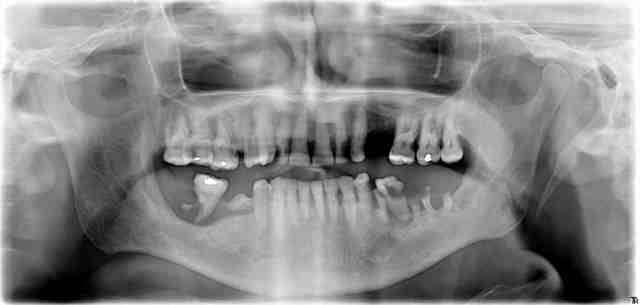

55 ans, infarctus, pontage, stens

et toujours 20 clopes par jour